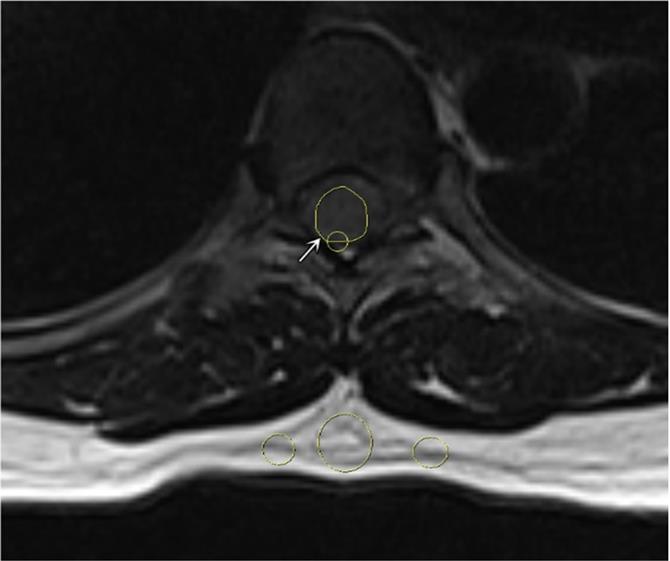

The tumor size was defined as the average of the anterior-posterior diameter and the greatest horizontal diameter on a single T2W slice [2]. The longitudinal spinal location of the tumor was defined as cervical, thoracic, lumbar, or sacral. The horizontal location of the tumor was defined as anterior, posterior, or lateral. The signal intensity (SI) of the tumor on T2W was measured, and maximum (T2max), minimum (T2min), and mean (T2mean) values were recorded. Pre-contrast and contrast-enhanced T1W (T1CE) SI values were measured, and the maximum (T1max and T1CEmax), minimum (T1min and T1CEmin), and mean (T1mean and T1CEmean) values were recorded in defined regions of interest (ROIs; Figure 1). The ROIs were hand-drawn and set with surrounding tumors on sagittal plane on T1W, T2W and T1CE to obtain the similar size of the ROI and to compare the tumor components on different sequences. At the largest area of the tumor, the ROI should cover at least two-thirds of the tumor diameter and should not contain any other surrounding structures (cerebral spinal fluid, bone, or ligamentum flavum). The SI for fat (SI fat) was determined by obtaining the mean value from three circular regions (covering 20-60 mm2) on the posterior side of the spinous process and both side pedicles. All of these values should be measured on the same slice, corresponding with the region in which the tumor size is the largest (Figure 2) [15]. The tumor to fat SI ratio on T2W (rTF) was calculated as SI tumor/SI fat.

Figure 2

A representative region of interest on the tumor (white arrow) and 3 subcutaneous regions on axial T2-weighted image.